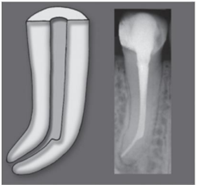

Um degrau é uma anomalia formada na parede

de um canal radicular antes de atingir o ápice e

sem qualquer conexão com o ligamento

periodontal. Sua ocorrência é mais comum nas

porções iniciais dos canais radiculares curvos.

A parede externa do canal sofre desgaste,

resultando na configuração de um plano

horizontal conhecido como degrau. Esse

incidente dificulta ou até mesmo impossibilita

o avanço do instrumento em direção apical no

canal radicular.